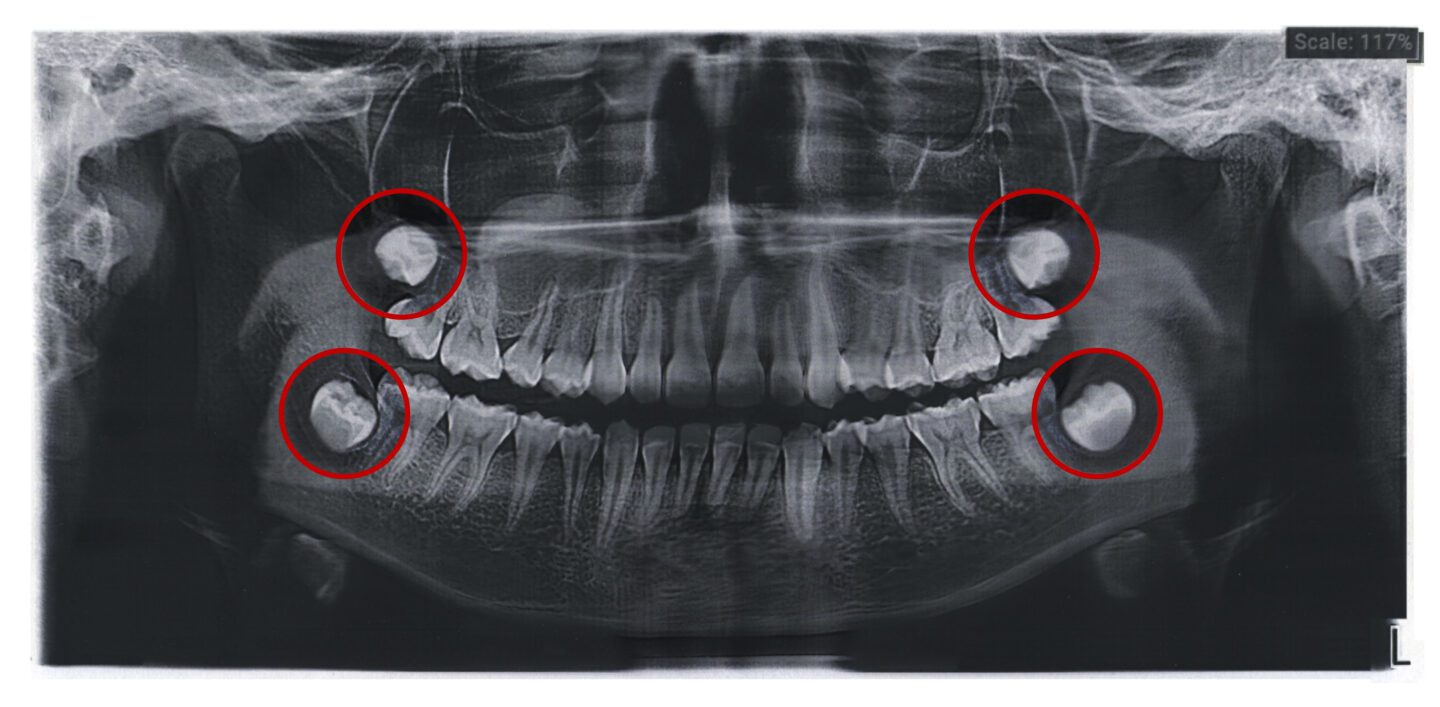

One of the most frequent issues associated with wisdom teeth is impaction, where the teeth do not fully emerge through the gums. This can occur because there isn’t enough room in the mouth for the teeth to develop normally. Impacted wisdom teeth can be painful and lead to infection. Removing these teeth can provide relief and prevent further dental complications.

Fun fact: Not everyone develops a complete set of four wisdom teeth; some may have fewer or none. This variation is quite normal and can be attributed to genetic differences. For those with only a few wisdom teeth, the decision to remove them still depends on whether they pose potential problems such as impaction, crowding of other teeth, or difficulties with oral hygiene. Even if there are fewer wisdom teeth, it’s essential to monitor them with the help of a dental professional to ensure they do not disrupt the overall health of your mouth.